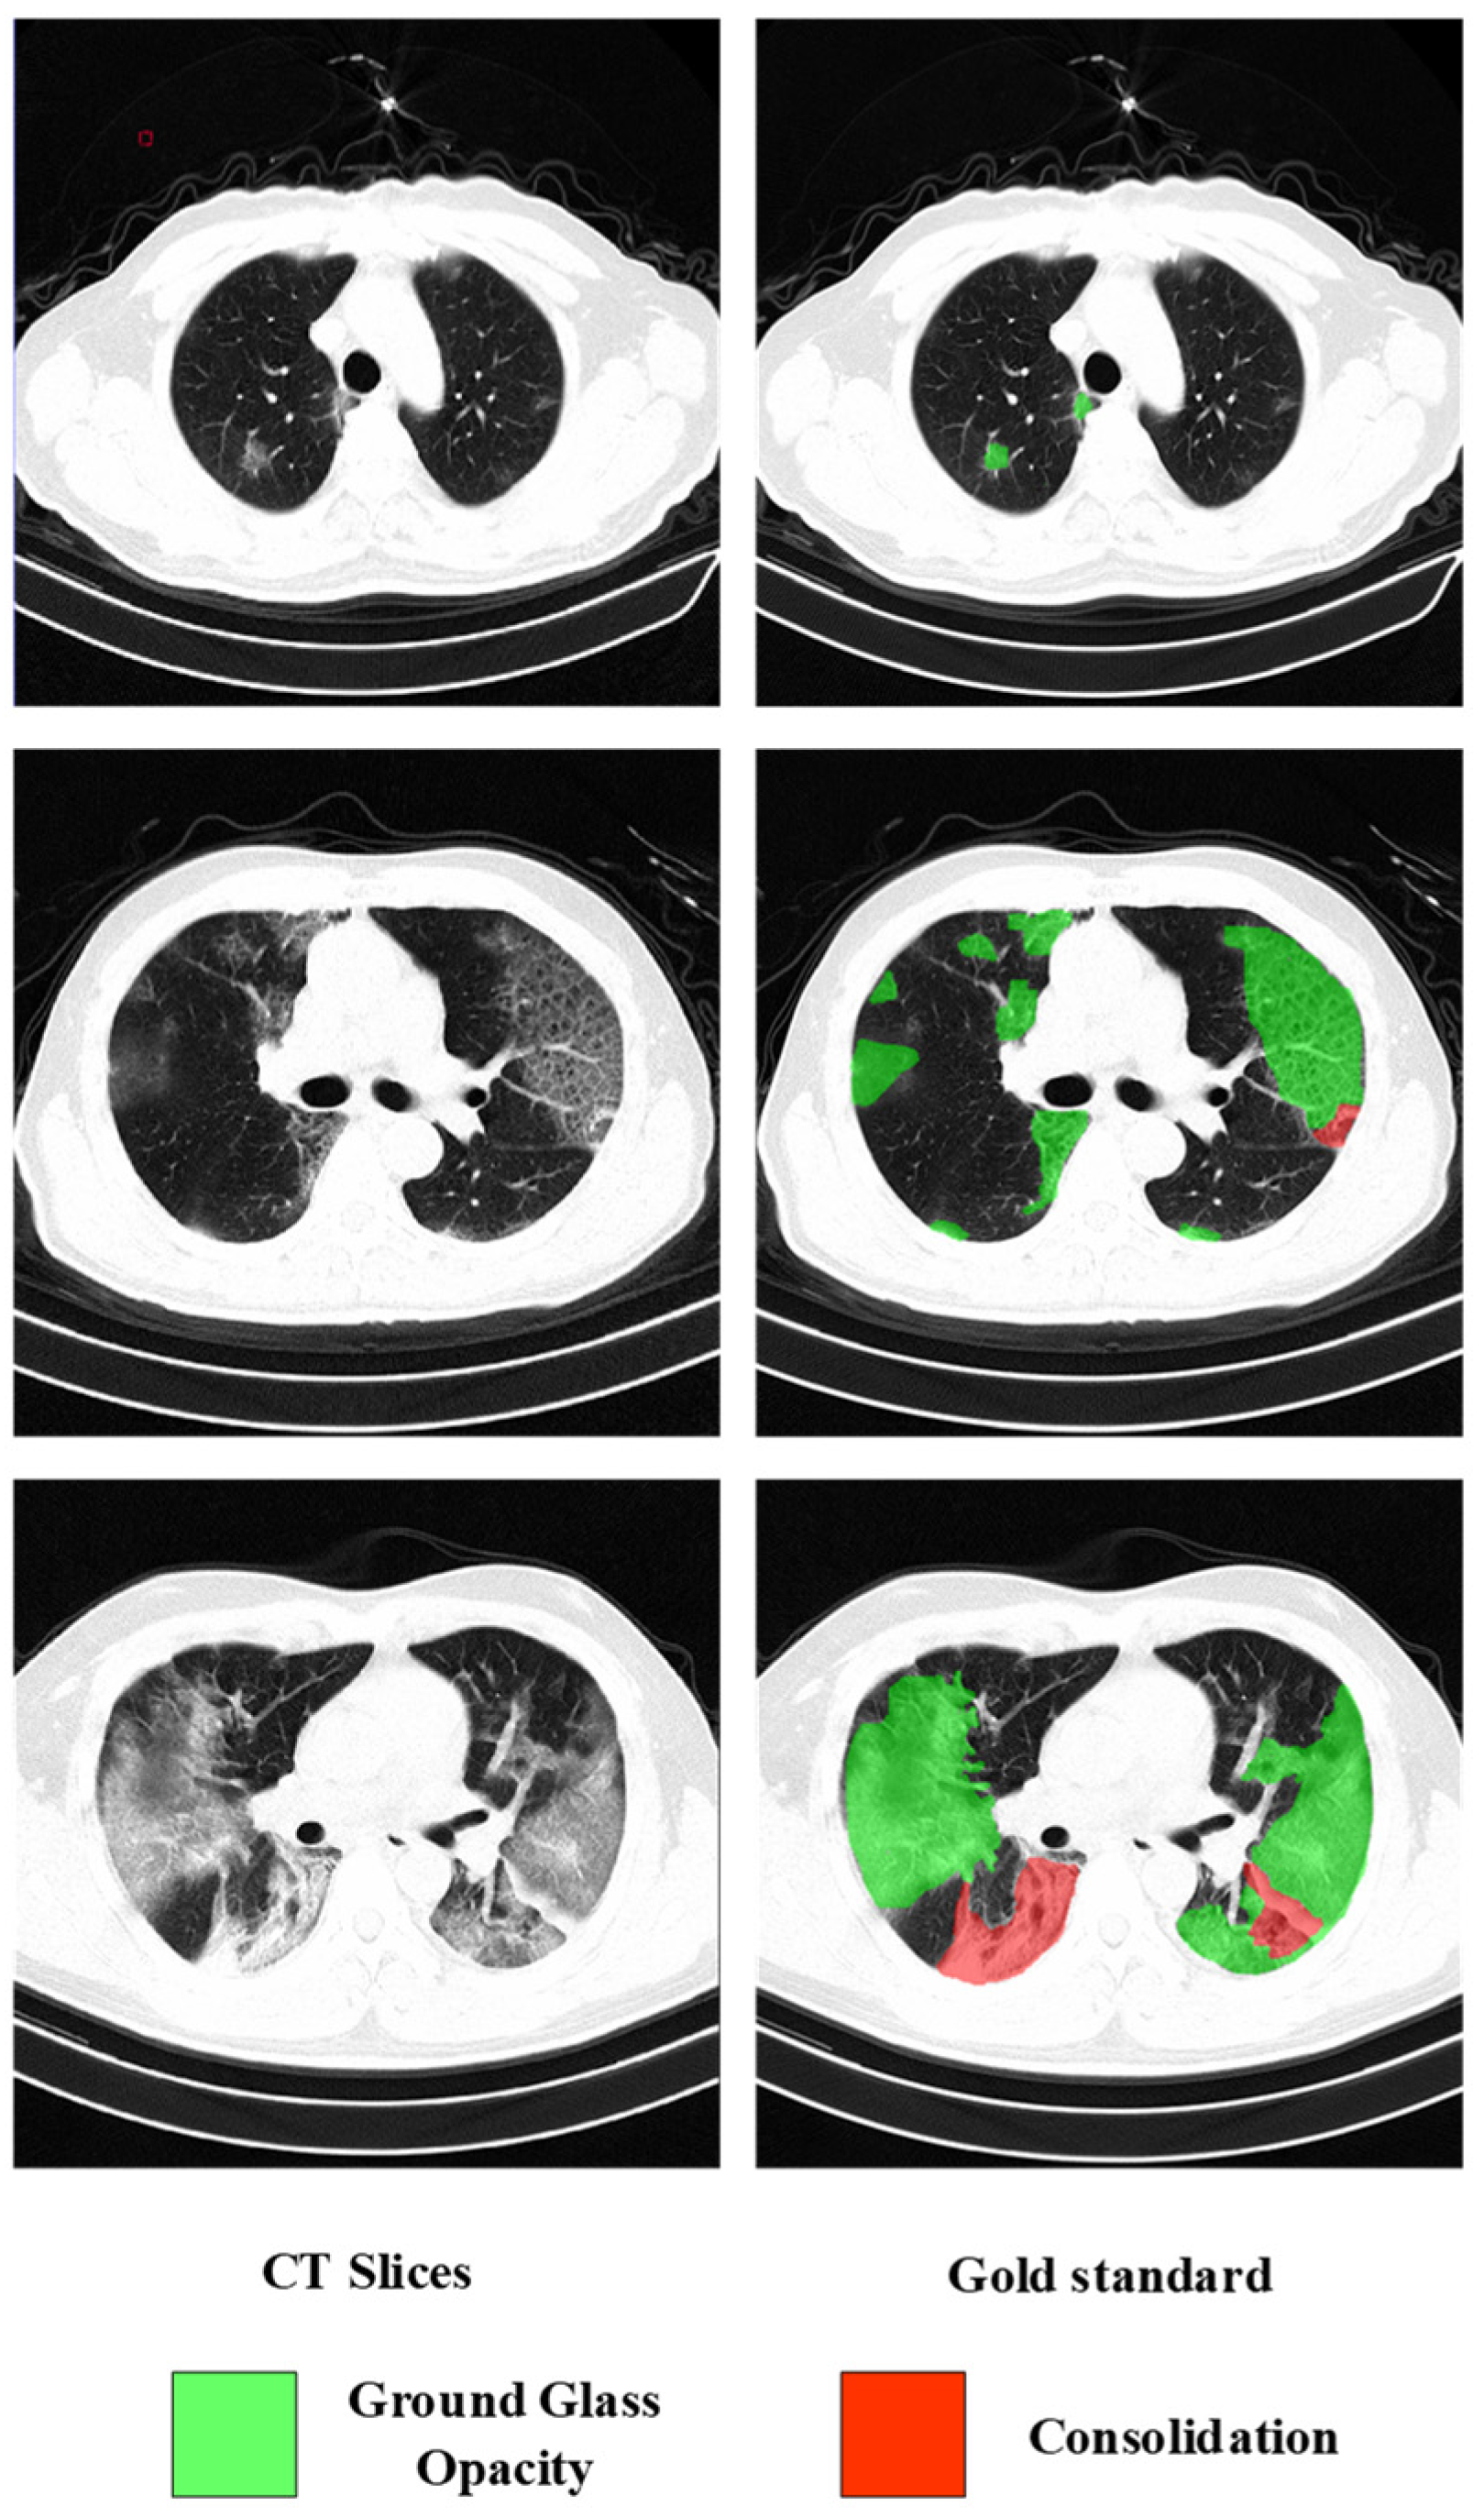

4.1.2. Lesion Segmentation Dataset (COVID19-Seg)

4.1.3. Lesion Segmentation Dataset (CC-COVID)

4.5. Segmentation Results of COVID-19 Lesions